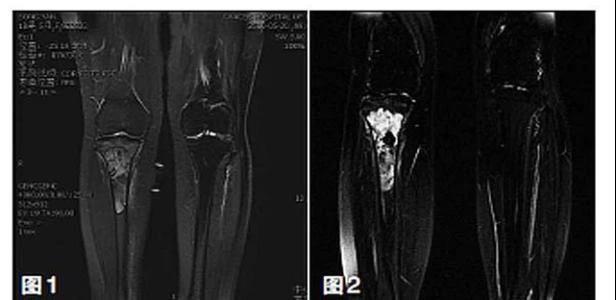

新輔助化療的目的是盡早殺滅遠(yuǎn)處微小轉(zhuǎn)移灶,縮小腫瘤及周圍炎性水腫反應(yīng)區(qū),以利于后續(xù)的保肢手術(shù);觀察腫瘤對化療的敏感性,為進(jìn)一步指定個(gè)體化的術(shù)后化療方案奠定基礎(chǔ)。骨肉瘤新輔助化療下的保肢治療如下圖所示: